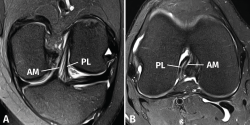

Las secuencias FSE 3D isotrópicas con diferentes nombres comerciales (Space®, Cube®, Vista®, MPV®...) permiten realizar reconstrucciones multiplanares, incluyendo planos oblicuos adaptados al trayecto del LCA(10,11,12,13,14). Estudios recientes muestran que estas secuencias tienen una precisión similar a las secuencias 2D convencionales en la valoración de las lesiones intraarticulares de rodilla. Sin embargo, las imágenes reconstruidas con estas secuencias FSE 3D muestran un mayor grado de distorsión geométrica que dificulta valorar específicamente las lesiones parciales del LCA. La realización de cortes milimétricos oblicuos 2D DP con campo de visión reducido en los planos coronal (siguiendo el trayecto del LCA) y axial (perpendiculares al LCA) permiten obtener imágenes de alta resolución espacial que facilitan una valoración más fiable de las lesiones parciales del LCA(15)(Figura 3).

Figura 3. Anatomía normal del ligamento cruzado anterior (LCA) en cortes oblicuos de resonancia magnética (RM). A: corte oblicuo coronal de RM potenciado en densidad protónica (DP) con supresión grasa adaptado al trayecto del LCA que muestra la anatomía bifascicular normal; B: corte oblicuo axial de RM potenciado en DP con supresión grasa perpendicular al trayecto del LCA que permite valorar el estado de ambos fascículos. AM: fascículo anteromedial; PL: fascículo posterolateral.